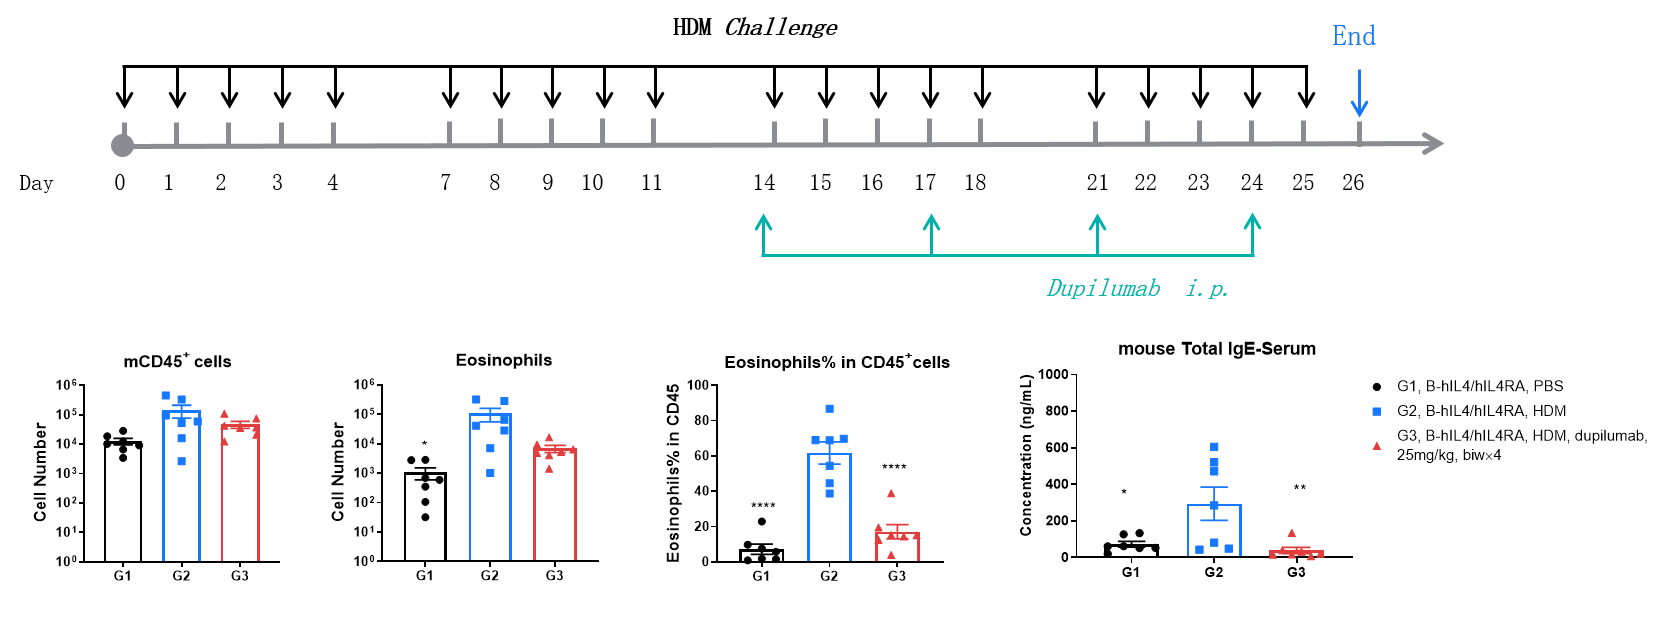

Efficacy Evaluation of the anti-human IL4RA (dupilumab) (in house) in HDM-induced Asthma Model of B-hIL4/hIL4RA mice. (A) The number of CD45+ cells in BALF. (B) The number of eosinophils in BALF. (C) The proportion of eosinophils to CD45+ cells. The results showed that after challenge with HDM, the leukocyte infiltration of mice in G4 model group was significantly increased compared with G3 control group, and their eosinophil content was significantly increased, suggesting that the model was successfully established. After administration of 25 mg/kg dupilumab (in house), the numbers of CD45+ cells and eosinophils were significantly lower compared with the G3 model group. (D) Serum was taken at the end of the experiment and total IgE levels were measured. The results showed that the levels of total IgE in G4 model group were significantly increased compared with G3 control group, suggesting successful modeling. Total IgE levels were significantly lower after administration of dupilumab (in house) drug compared with the G4 model group.

Efficacy Evaluation of the anti-human IL4RA (dupilumab) (in house) in HDM-induced Asthma Model of B-hIL4/hIL4RA mice. ( A) The number of CD45+ cells in BALF. (B) The number of eosinophils in BALF. (C) The proportion of eosinophils to CD45+ cells. The results showed that after sensitization and challenge with HDM, the leukocyte infiltration of mice in G2 model group was significantly increased compared with G1 control group, and their eosinophil content was significantly increased, suggesting that the model was successfully established. After administration of 25 mg/kg dupilumab (in house), the numbers of CD45+ cells and eosinophils were significantly lower compared with the G2 model group. (D) Serum was taken at the end of the experiment and total IgE levels were measured using ELISA. The results showed that the levels of total IgE in G2 model group were significantly increased compared with G1 control group, suggesting successful modeling. Total IgE levels were significantly lower after administration of dupilumab (in house) drug compared with the G2 modeling group. * P?

H&E staining in the lungs of asthmatic mice. In contrast to the G1 untreated group, the HDM-treated G2 model animals showed asthma-related pathological changes as demonstrated by vascular and peribronchial mixed eosinophil cell infiltration (a) and inflammatory cell infiltration (b) in some bronchi. After administration of dupilumab (in house), the numbers of mCD45+ cells and eosinophils were significantly lower compared with the G2 model group. *** P?

H&E staining in the lungs of asthmatic mice. In contrast to the G1 untreated group, the HDM-treated G2 model group showed asthma-related pathological changes as demonstrated by vascular and peribronchial mixed inflammatory cell infiltration (b) and mucus (a) formation in some bronchi. After administration of dupilumab (in house), the numbers of CD45 + cells and eosinophils were significantly lower compared with the G2 model group.